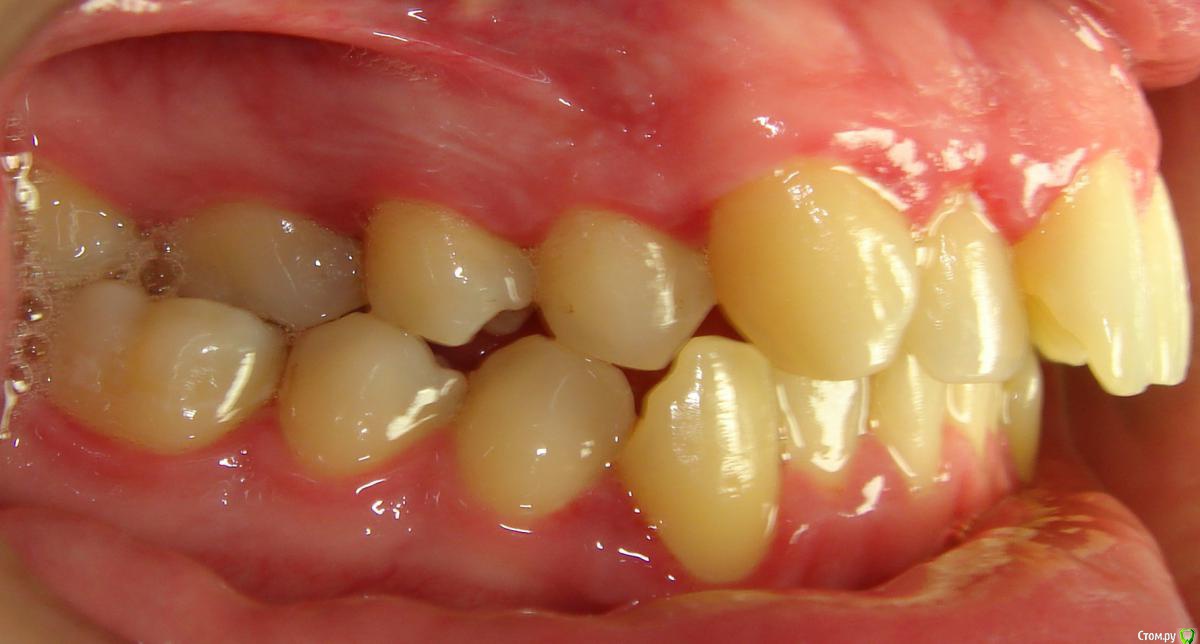

Здравствуйте, Коллеги. Вот такой вот случай, пациент 32 года. Изначально, хотел дистализировать в первом сегменте с целью апрайтинга 13 - 16, провести апрайтинг боковых зубов н/ч, затем САРПЕ и MEAW, понятно, что восьмерки долой еще до лечения. Но потом увидел форму корней 37, 47 (это не искажение, по КТ они и правда такие) и кисты прорезывания за ними. В связи с этим мне кажется, что апрайтинг снизу невозможен, так как эти верхушки никуда меня не пустят, разве что ввиду проблем с пародонтом семерки тоже уйдут. Вопрос: что делать??? Даже если отбросить мультилуп и готовить его на ортогнатию, то апрайт все-равно нужен, как поступить? Заранее спасибо!

P.S.: Забыл... сверху семерки такие же.